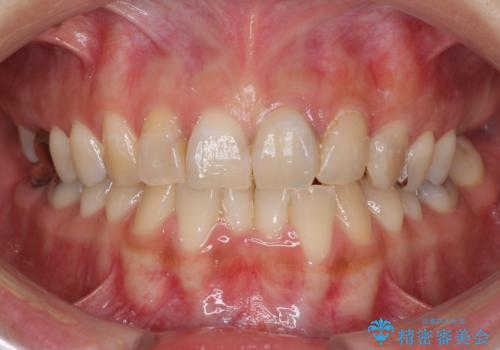

[ 前歯のねじれ・がたつき ] マウスピース矯正

![[ 前歯のねじれ・がたつき ] マウスピース矯正の症例 治療前](https://seimitsushinbi.jp/wp/wp-content/uploads/2024/02/4007c6479f6bce11863dcdd32ed5e39b-500x350.jpg?v=1708502552)

![[ 前歯のねじれ・がたつき ] マウスピース矯正の症例 治療後](https://seimitsushinbi.jp/wp/wp-content/uploads/2024/02/e7a01485e4f4dd0da04705fde4cc34cc-500x350.jpg?v=1708502585)